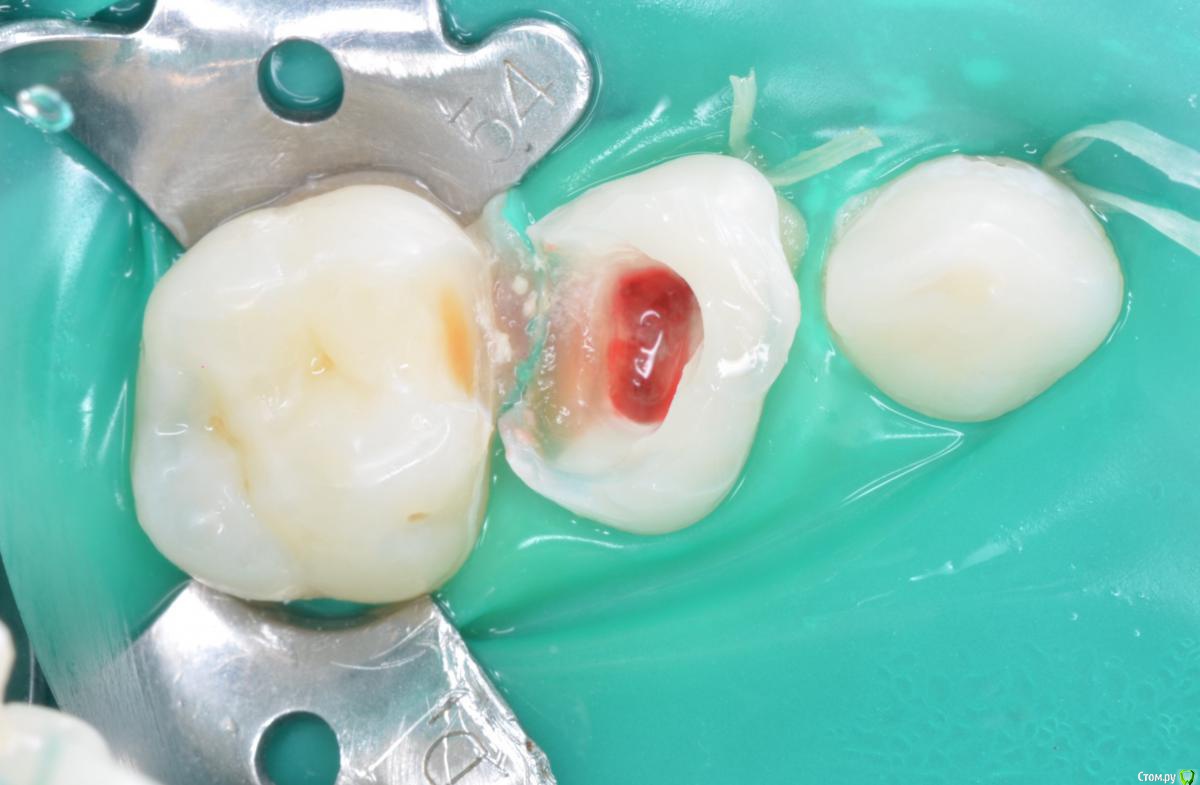

CRAZYDUCK Опубликовано 22 мая, 2018 Автор Поделиться Опубликовано 22 мая, 2018 Сначала текст , ниже фото .Даша , 5,5 лет . Лечение кариеса 5.5, кариеса 5.3 , необратимый пульпит 5.4. Продолжительность 1час 30 минут ( с момента входа в кабинет, выбора мультика и до расставания).«Скрытый» кариес медиальной контактной поверхности 5.5 подтверждён RVG. Я указала на него синими стрелочками ( листайте). 5.3 обработала рондофлекс и немного микромотором .5.4 - видно , что после ампутации гемостаза нет( полость заполнена кровью). Экстирпация машинный sx, ручные файлы 25.02; промываю гипохлорит 3%. В каналах Йодотин.культя 5.4 восстановлена IRM. Коронку фиксирую на айрекс-цем.Контрольный снимок. 1 Ссылка на комментарий

CRAZYDUCK Опубликовано 22 мая, 2018 Автор Поделиться Опубликовано 22 мая, 2018 Фото. 2 Ссылка на комментарий